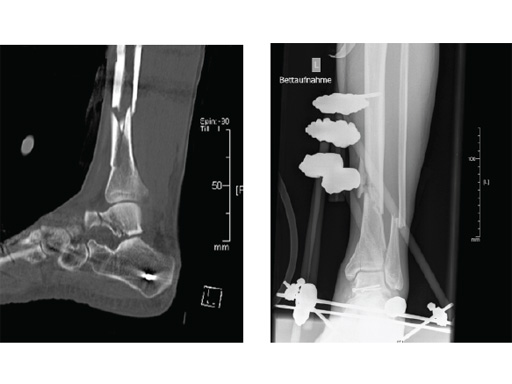

Case 2: Grade II open distal tibial fracture in a polytraumatized 52-year-old man.